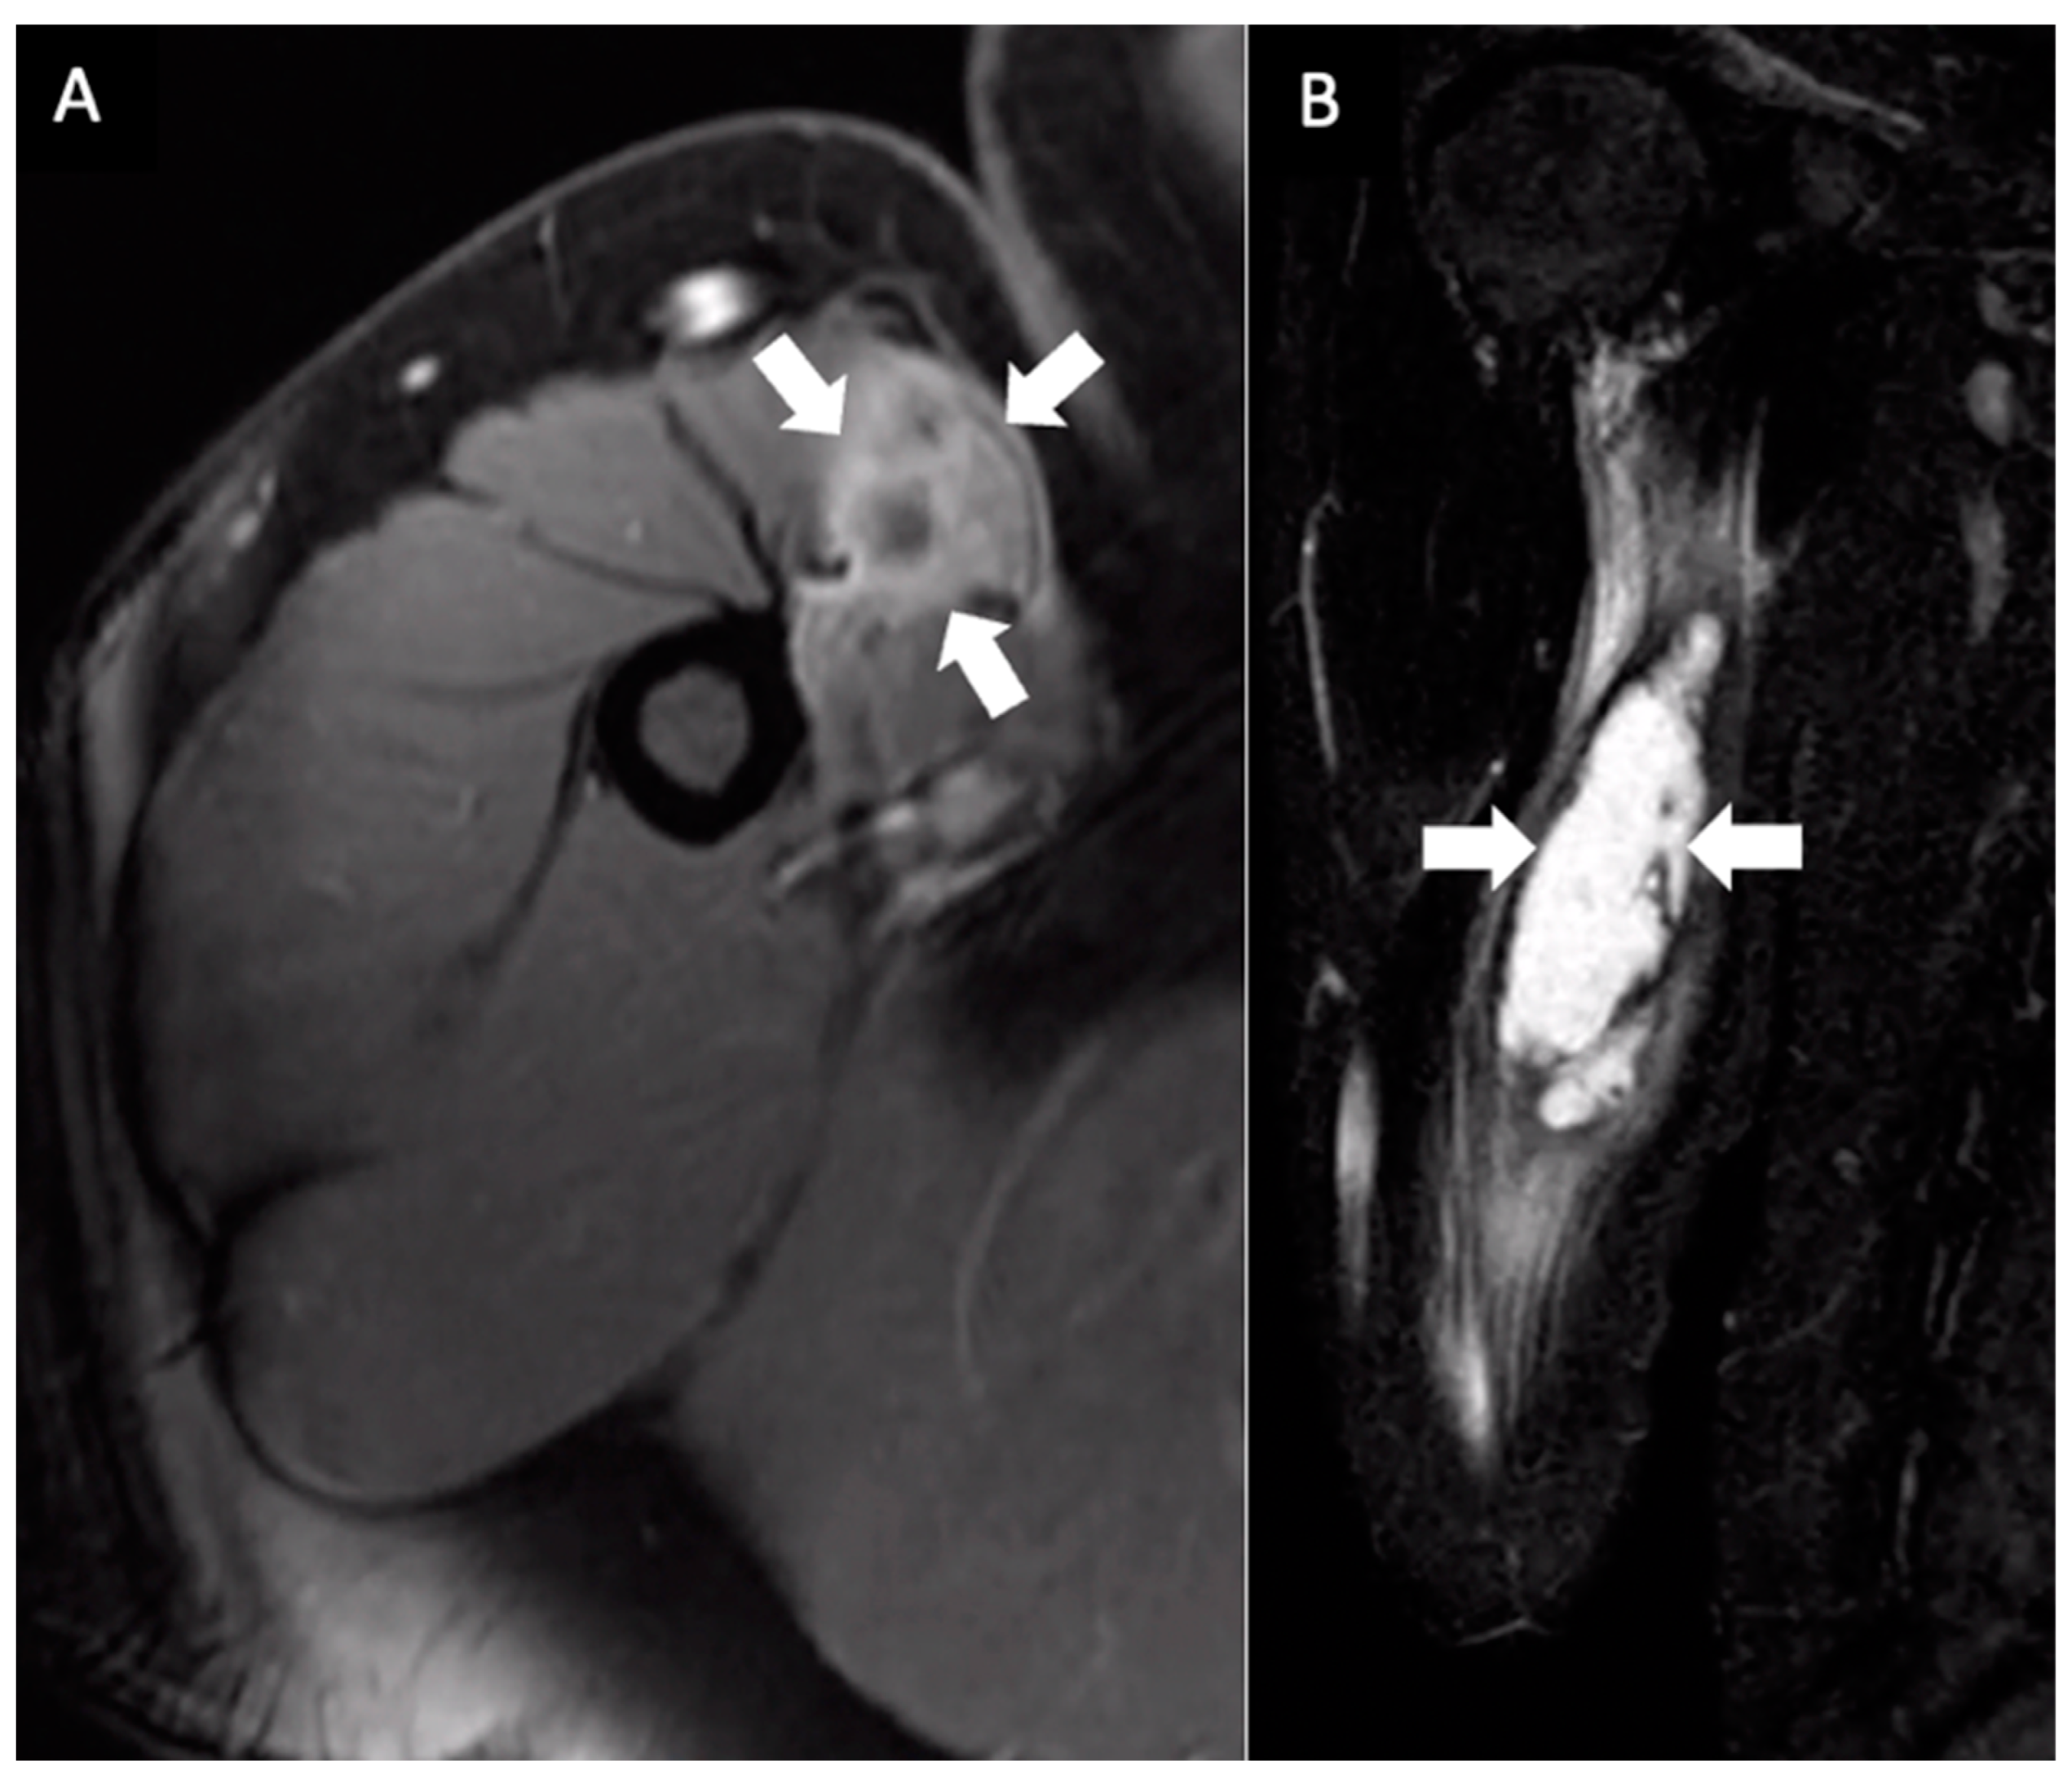

His primary care physician referred him to an orthopedic surgeon to evaluate his right upper arm. Physical examination at that time, two weeks later, was notable for a firm, clinically circumscribed, nontender mass in the right upper arm. Right shoulder active range of motion (ROM) was within the normal range, but passive range of motion was decreased. Given the MRI findings of an indeterminate mass, the orthopedic surgeon elected for a needle aspiration. An ultrasound-guided needle aspiration yielded 30 mL of turbid brown fluid, and a biopsy showed fibromuscular tissue with a chronic lymphoplasmacytic inflammatory infiltrate comprised of lymphocytes, plasma cells, and eosinophils. Immediately after the aspiration, there was a subjective improvement in the size of the swelling; as the patient stated, “the mass was not a golf-ball anymore”. However, a second MRI taken two weeks after the needle aspiration showed persistent 10 × 3.1 × 1.9 cm ill-defined fluid signals and peripheral enhancement in the proximal right biceps in the same location as on the first MRI (Figure 2). Given the persistent MRI findings and unclear diagnosis, a complete excision of the mass was accomplished in the following week. The pathology showed soft tissue and skeletal muscle with mild fibrosis and aggregates of inflammatory cells, consisting mostly of lymphocytes, plasma cells, and histiocytes. The cells showed no atypia or cytological features of malignancy (Figure 3).

Figure 2. Multiplanar MRI of the right upper arm taken one month after identifying the mass and seven months after receiving the booster dose. Axial fast spin gradient echo postcontrast (A) and coronal STIR (B) images show an ill-defined central fluid signal measuring 10 × 3.1 × 1.9 cm with prominent peripheral enhancement (arrows).